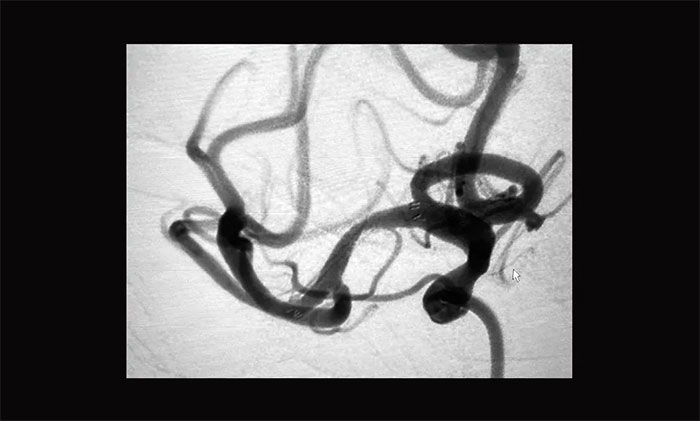

患者血管迂曲,张琪博士在周林华医生协助下,经过多次尝试后,微导管、微导丝终于成功到达狭窄部位,顺利进行球囊扩张并以支架拉栓,30分钟后再次行造影提示右侧大脑中动脉M1段无明显改善,遂决定行右侧大脑中动脉支架置入术。

支架导管到位右侧大脑中动脉M2段上干,随后经微导管顺利置入支架,造影见支架贴壁良好,完全覆盖狭窄段,狭窄改善明显,支架内血流通畅,远端血流良好,手术顺利完成。

▲ 术后DSA影像:右侧大脑中动脉血流恢复

术后,患者意识清楚,语言流利,左上肢无力感消失,四肢活动自如,由于经桡动脉造影,术后即可下床行走,无需制动24小时。复查颅脑CT未见出血及新发梗死,目前患者正在康复中。